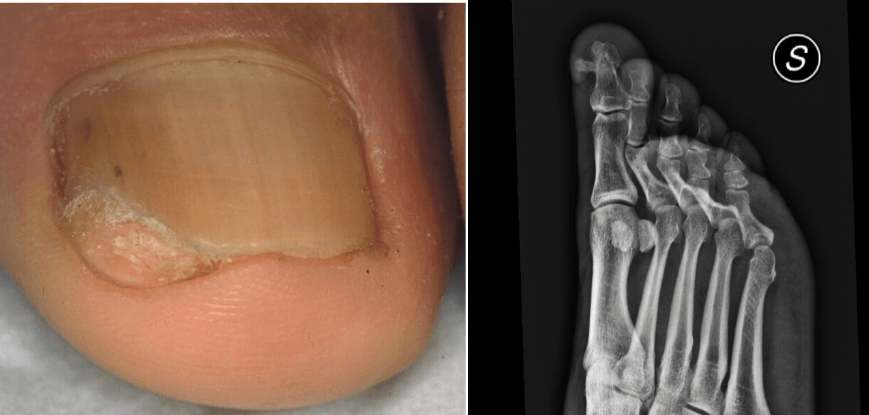

Le indicazioni chirurgiche della patologia ungueale sono diverse:

- biopsie incisionali della matrice e del letto ungueale per ottenere una diagnosi istologica;

- interventi ablativi sulla matrice ungueale per la correzione delle deformità della lamina;

- interventi di fenolizzazione della matrice ungueale per il

- trattamento delle unghie incarnite;

- asportazione di neoplasie benigne e maligne dell’unità ungueale;

- asportazione di esostosi sub ungueali;

- asportazione dell’unità ungueale.

Un altro ambito di eccellenza dell’attività chirurgica del Dr. Fanti è la chirurgia ungueale, una disciplina che richiede una conoscenza approfondita dell’anatomia e della fisiologia dell’apparato ungueale. Gli interventi vengono eseguiti con tecniche anestesiologiche mirate, che garantiscono un’efficace analgesia riducendo al minimo la sensazione di dolore.

Le principali indicazioni comprendono biopsie della matrice e del letto ungueale, correzione delle deformità della lamina, fenolizzazione per il trattamento dell’unghia incarnita, nonché l’asportazione di neoplasie benigne e maligne o di esostosi subungueali.

Il Dr. Fanti ha inoltre sviluppato

nuove tecniche di chirurgia laser ungueale, che consentono una maggiore precisione operativa e un miglior recupero funzionale ed estetico. Ogni procedura viene studiata sulla base della patologia e delle caratteristiche individuali del paziente, per garantire un equilibrio ottimale tra efficacia terapeutica e risultato estetico.